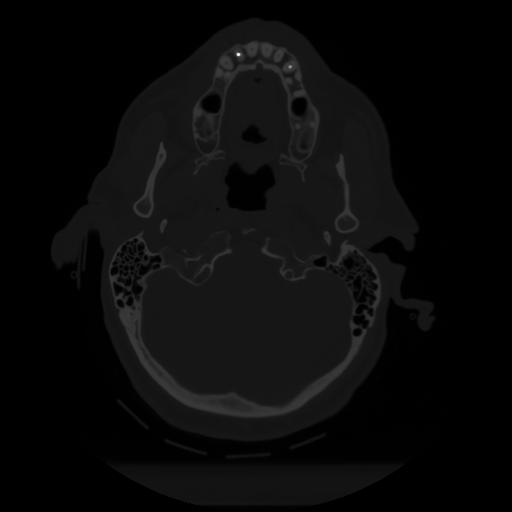

12 P.BLANDAS,,Vol,0.5,P.BLANDAS,,